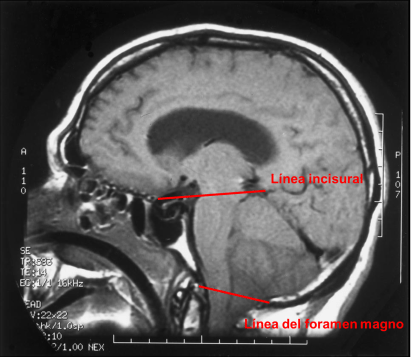

En la Imagen 4 señalo la línea incisural y la línea del foramen magno. La línea incisural es la línea dibujada desde la parte anterior del tubérculo selar hasta la confluencia del seno sagital inferior, seno recto y vena de galeno. En condiciones normales deja el mesencéfalo practicamente en su totalidad por debajo de la misma. La línea del foramen magno es la línea dibujada desde la punta inferior del clivus hasta el labio posterior del foramen magno. En condiciones normales esta línea se encuentra por debajo del bulbo raquídeo y deja las amigdalas cerebelosas por encima.

En la imagen 5 podemos ver como el mesencéfalo queda practicamente por encima de la línea incisural lo que demuestra una herniación transtentorial superior y como por debajo de la línea del agujero magno desciende parte del bulbo raquídeo y las amigdalas cerebelosas lo cual demuestra una herniación amigdalina.